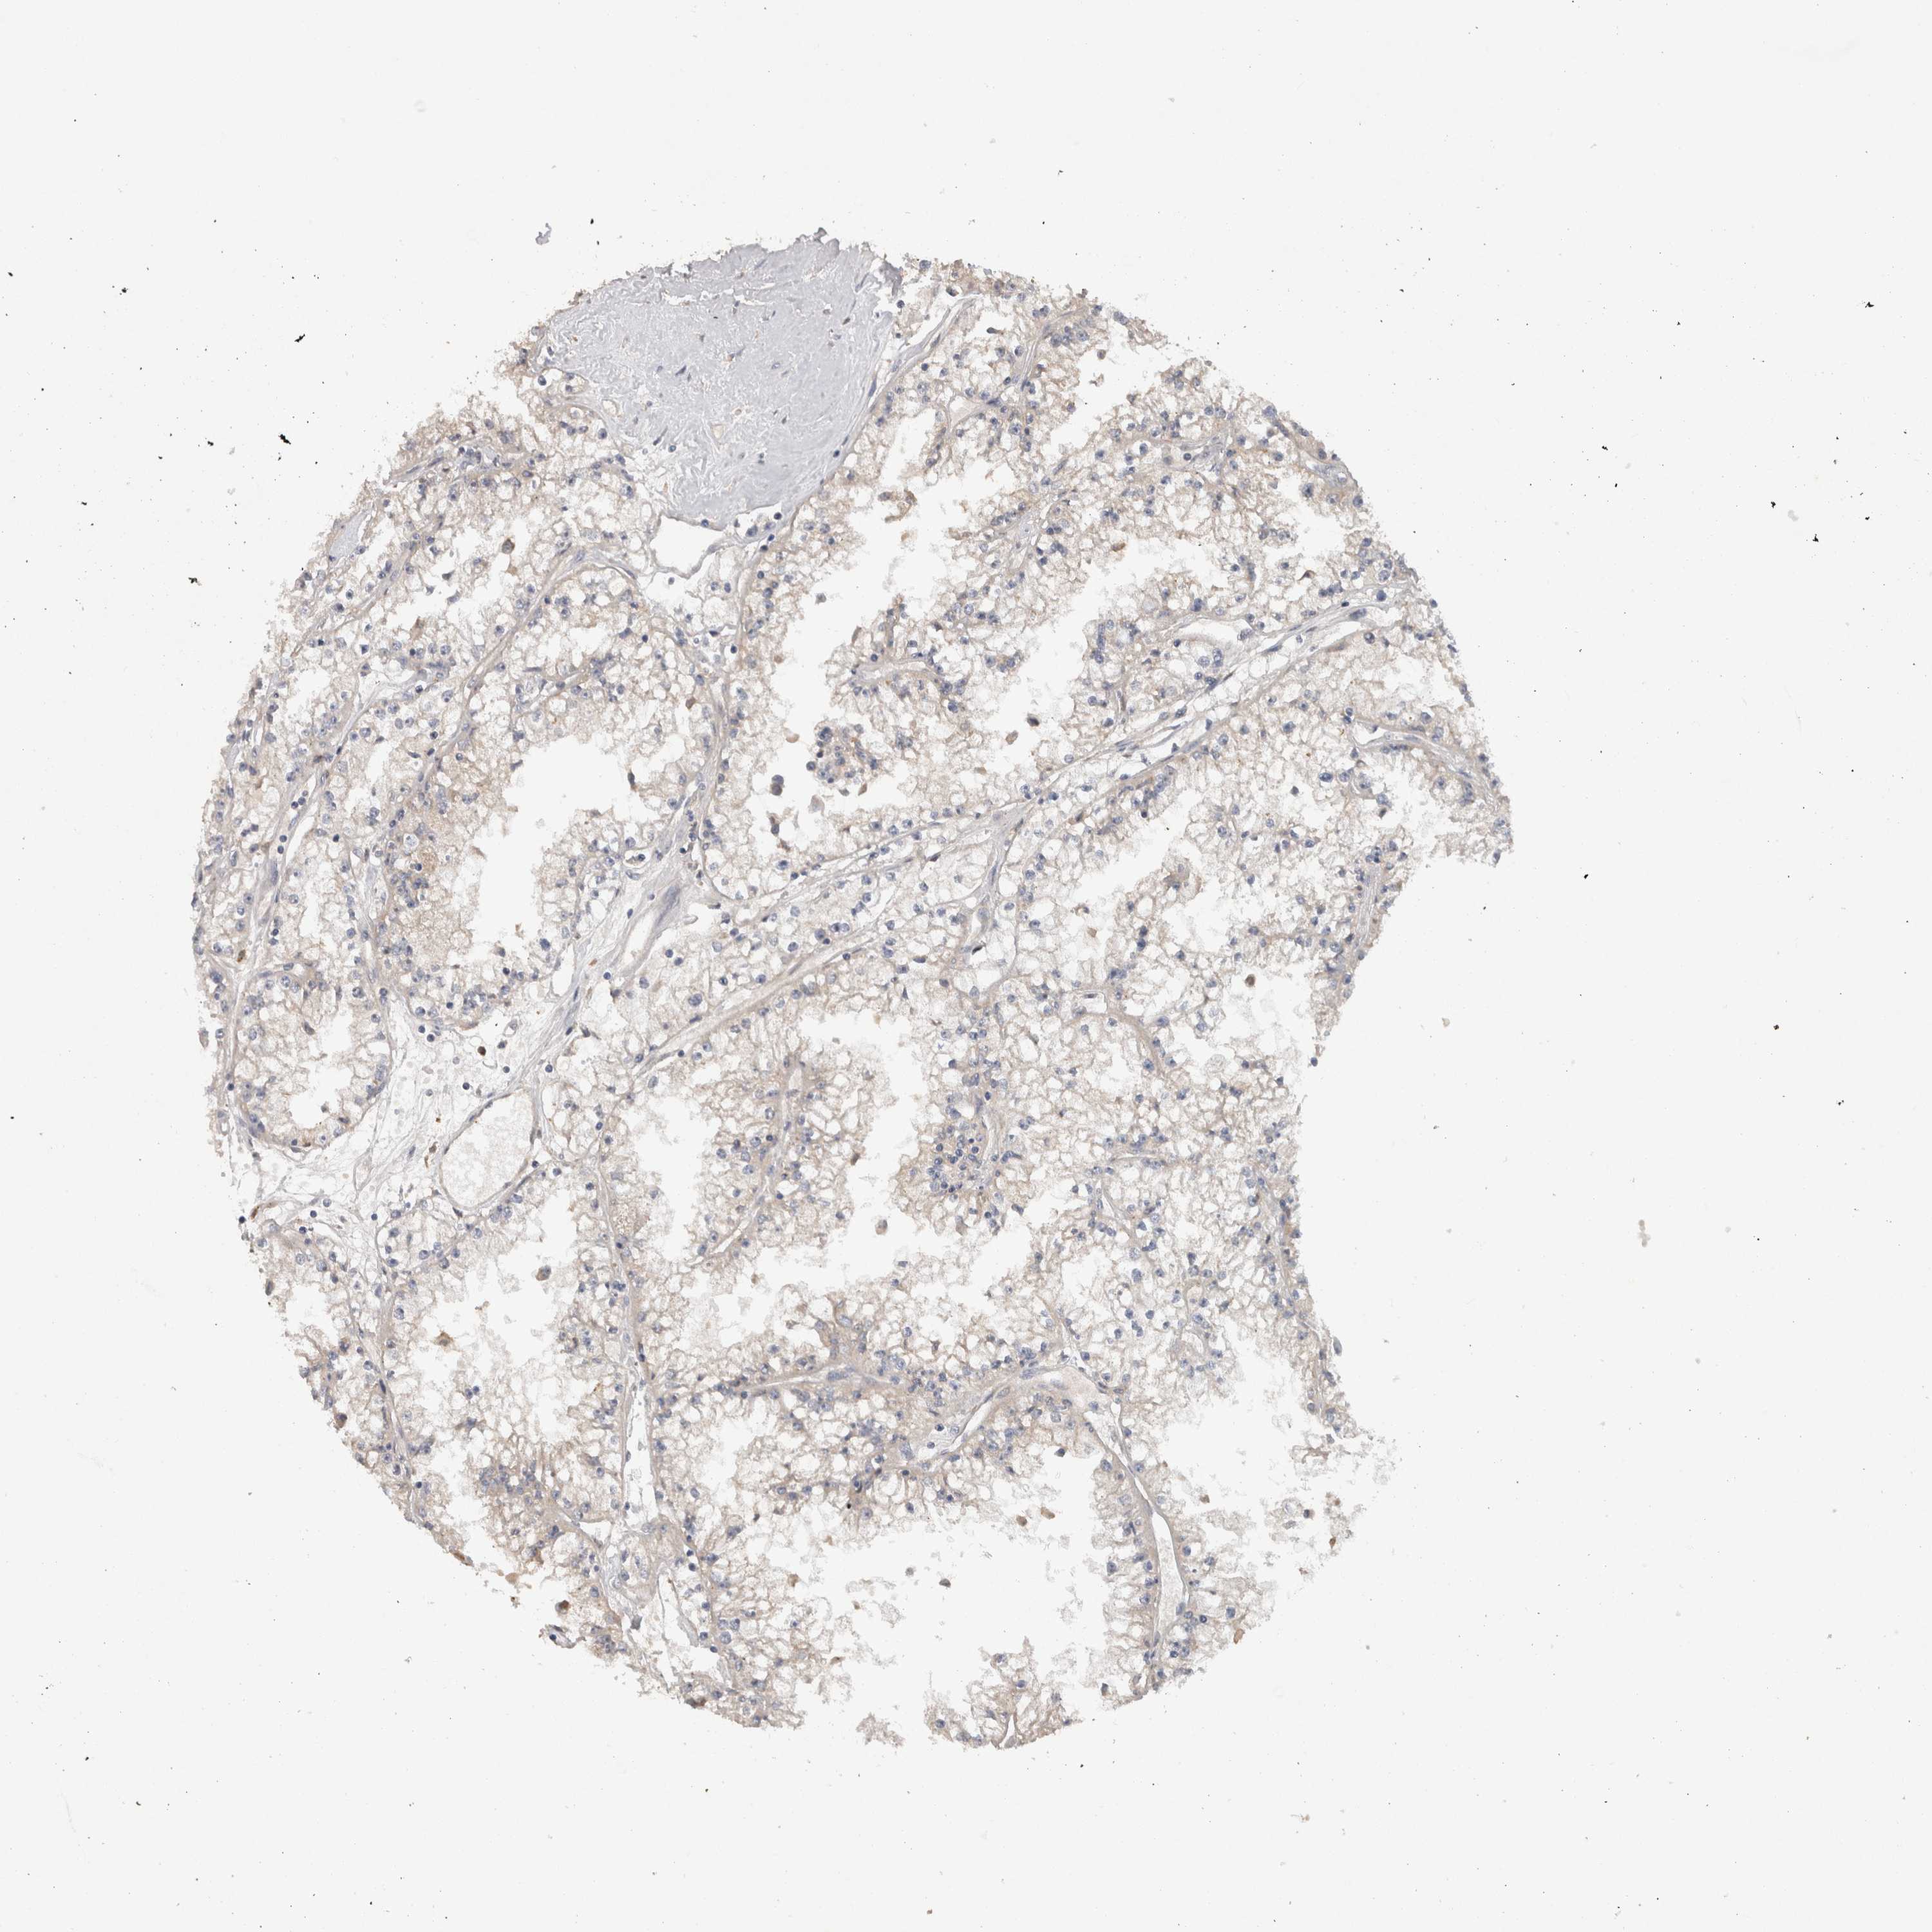

KIDNEY RENAL CLEAR CELL CARCINOMA (VALIDATION) - Interactive survival scatter ploti

The Survival Scatter plot shows the clinical status (i.e. dead or alive) for all individuals in the patient cohort, based on the same data that underlies the corresponding Kaplan-Meier plots. Patients that are alive at last time for follow-up are shown in blue and patients who have died during the study are shown in red.

The x-axis shows the expression levels (FPKM) of the investigated gene in the tumor tissue at the time of diagnosis. The y-axis shows the follow-up time after diagnosis (years). Both axes are complimented with kernel density curves demonstrating the data density over the axes. The top density plot shows the expression levels (FPKM) distribution among dead (red) and alive patients (blue). The right density plot shows the data density of the survived years of dead patients with high and low expression levels respectively, stratified using the cutoff indicated by the vertical dashed line through the Survival Scatter plot. This cutoff is automatically defined based on the FPKM cutoff that minimizes the p-score. The cutoff can be changed by dragging the vertical line or by entering a cutoff value in the square labeled "Current cut-off".

Under the Survival Scatter plot the p-score landscape (black curve; left axis) is shown together with dead median separation (red curve; right axis). Dead median separation is the difference in median mRNA expression between patients who have died with high and low expression, respectively. It is calculated as follows: median FPKM expression of dead patients with high expression - median FPKM expression of dead patients with low expression. This is intended to aid the user in visually exploring custom cutoffs and the associated p-scores and dead median separation.

Individual patient data is displayed and can be filtered by clicking on one or more of the category buttons on the top of the page. Categories describing expression level and patient information include: high, low, alive, dead, female, male and tumor stages. The scale of the x-axis can be toggled between linear and log-scale by clicking on the "x log" button. Mouse-over function shows TCGA ID, patient information and mRNA expression (FPKM) for each patient.

& Survival analysisi

Kaplan-Meier plots summarize results from analysis of correlation between mRNA expression level and patient survival. Patients were divided based on level of expression into one of the two groups "low" (under cut off) or "high" (over cut off). X-axis shows time for survival (years) and y-axis shows the probability of survival, where 1.0 corresponds to 100 percent.

HEXD is validated prognostic, high expression is favorable in Kidney Renal Clear Cell Carcinoma (validation)

: 10.61

Average pTPM 10.5

Number of samples 100